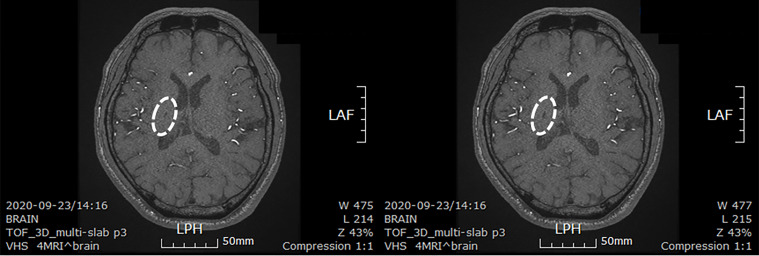

患者在干細(xì)胞移植后約30個月拍攝腦部CT圖像以確認(rèn)病灶的大小。病灶縮小至0.6cm×0.3cm(圖4)。